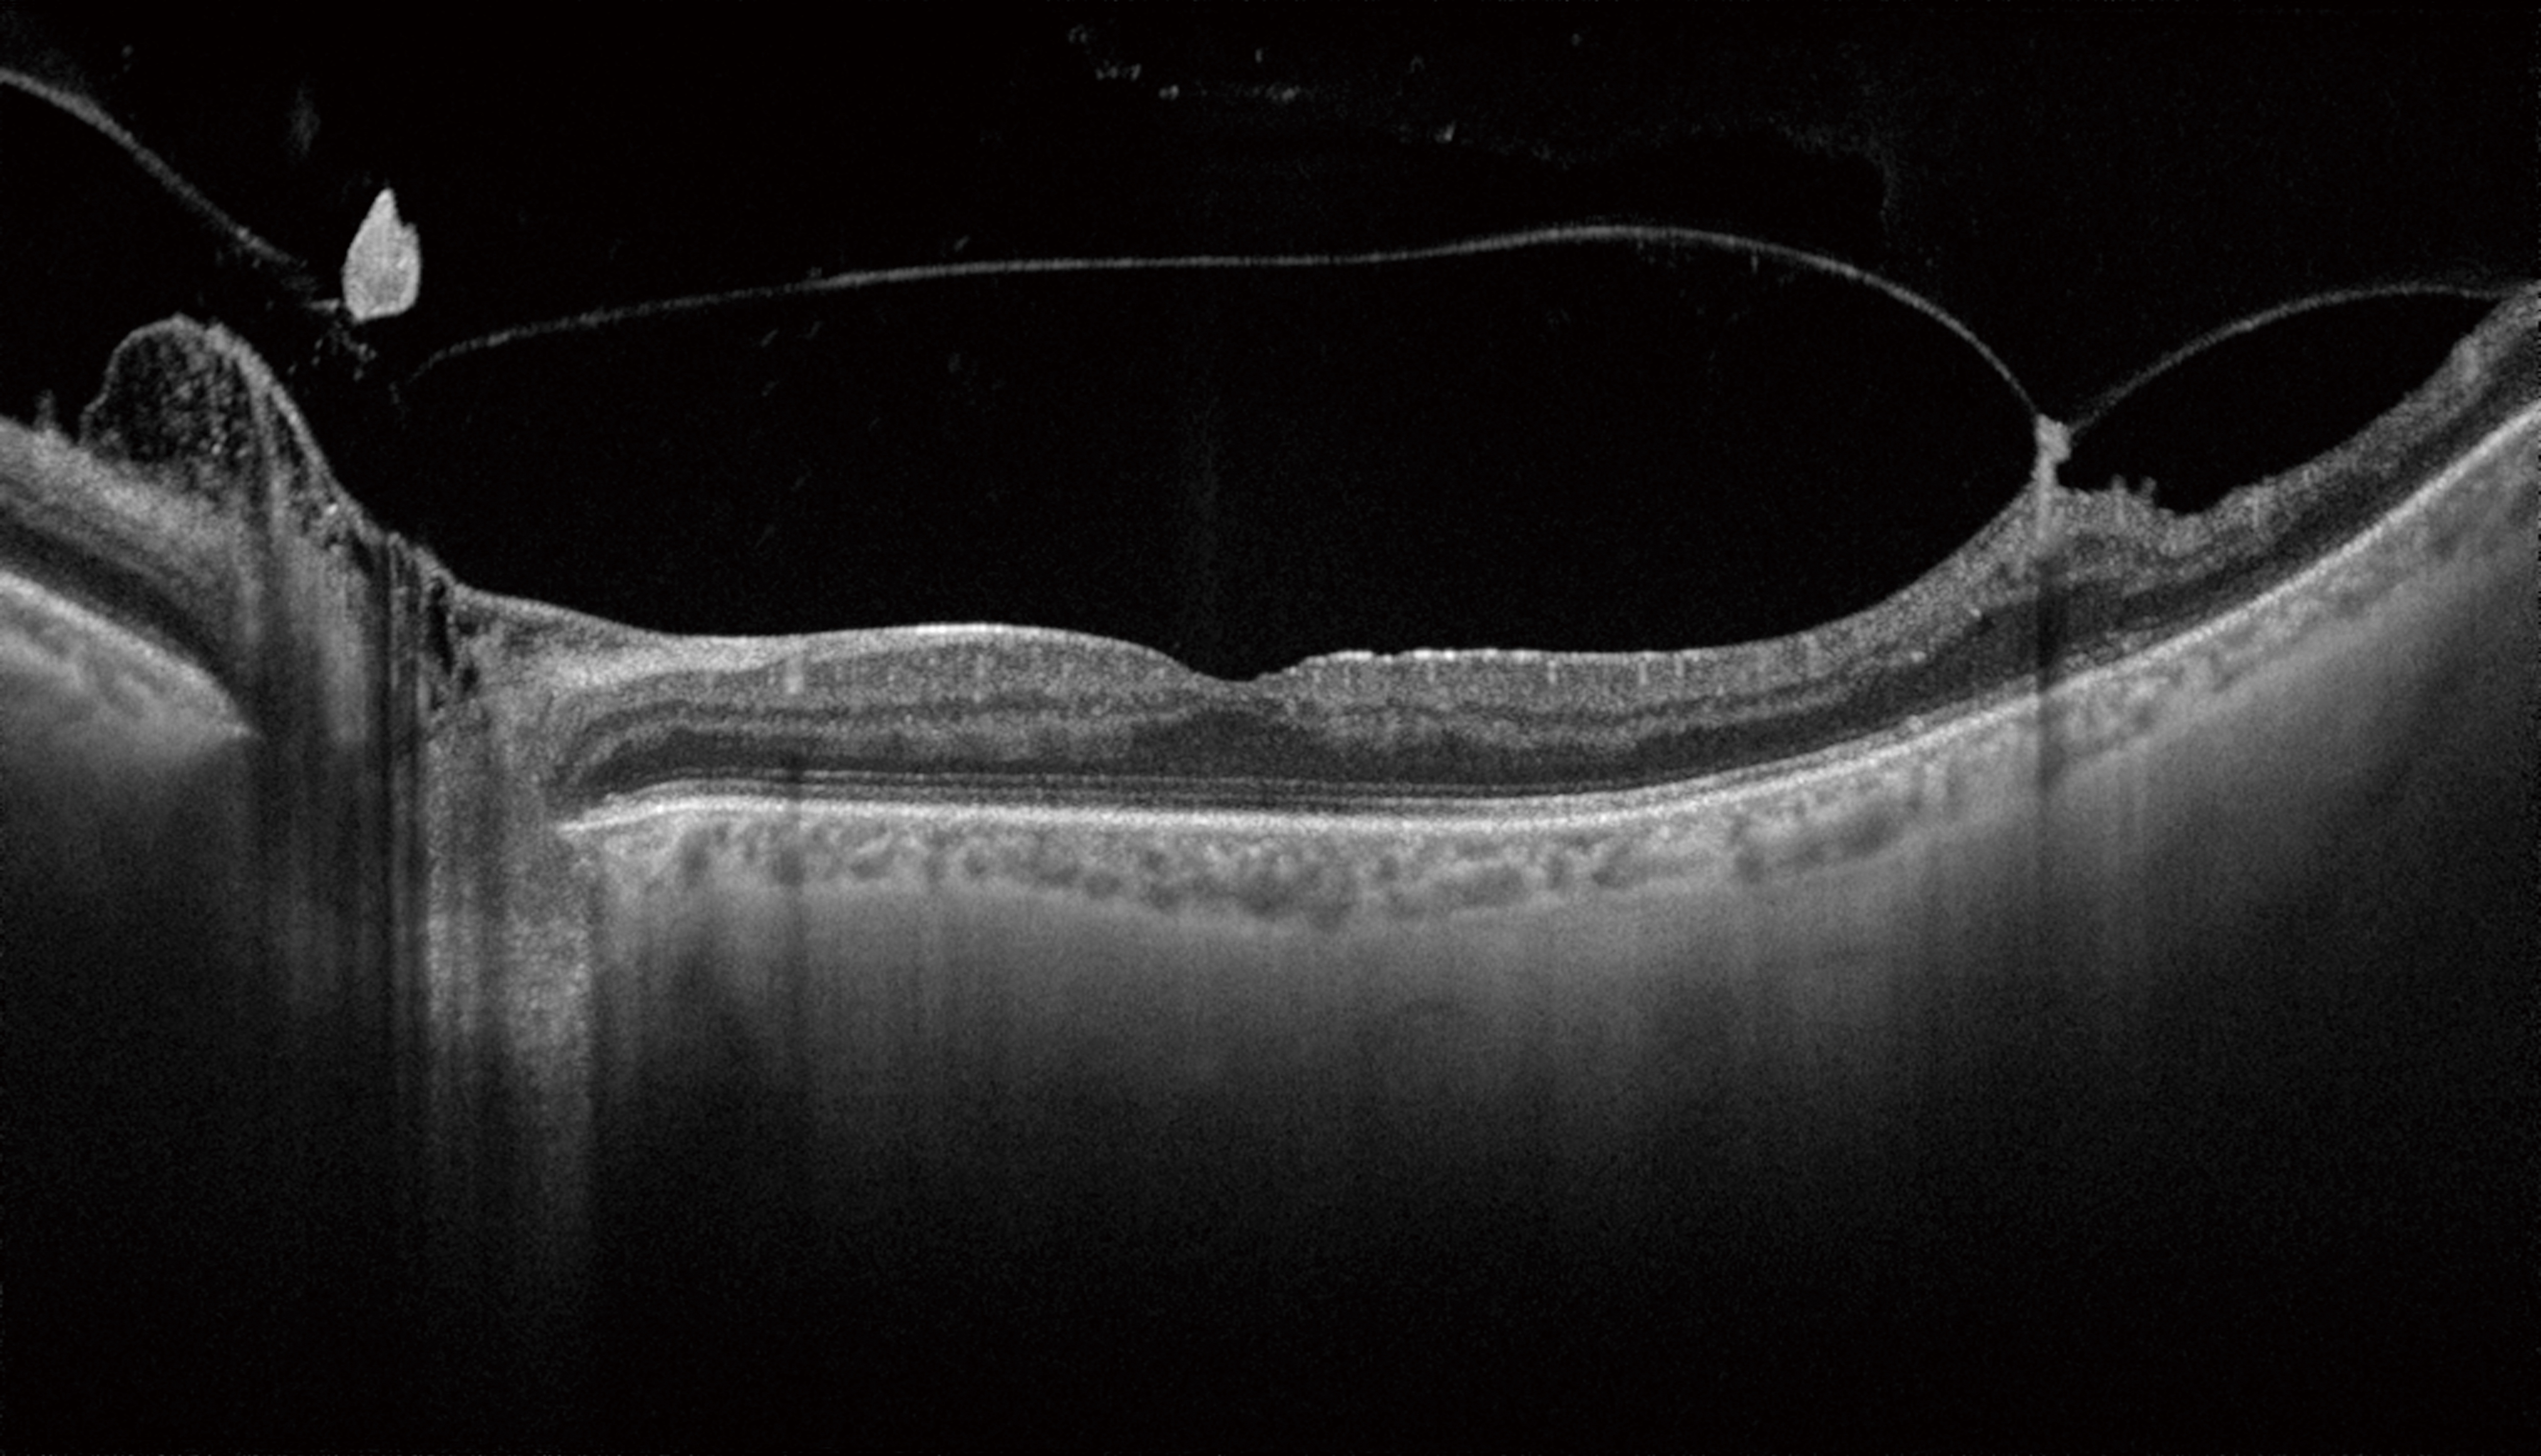

Уникальное сочетание нового механизма получения ОКТ-снимков SWEPT Source и сканирующего луча в инфракрасном диапазоне (1050 нм) позволяет получить качественный ОКТ снимок структур заднего отрезка глаза: стекловидного тела, сетчатки, хороидеи и склеры – на одном скане. Эта особенность сокращает время исследования за счет отказа от получения дополнительных снимков для получения снимков высокой четкости.

Большая проникающая способность инфракрасного излучения позволяет получить снимки даже в случае наличия помутнений в прозрачных средах глаза (катаракта, кровоизлияния и т.д.).

- Улучшенная визуализация глубоких слоев заднего отрезка, включающих хороидею и склеру за счет инфракрасного источника света 1050 нм, в том числе в случае помутнений в оптических средах